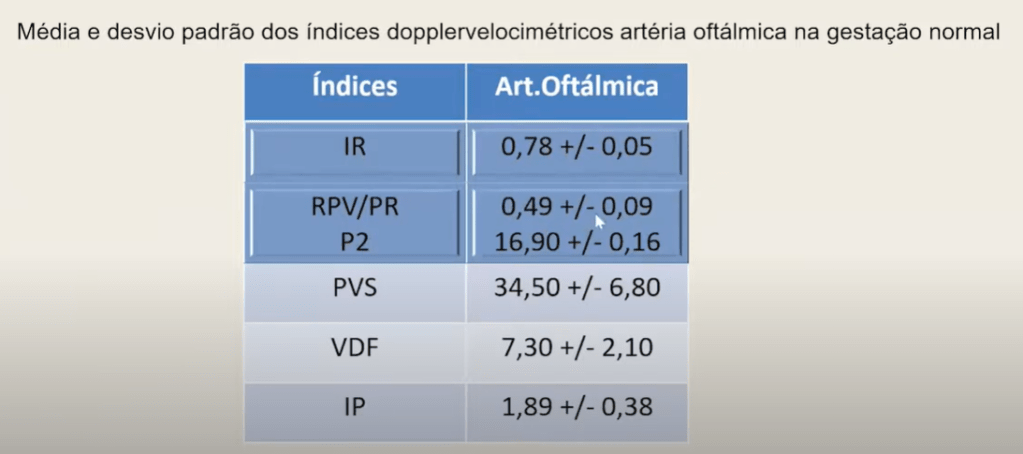

🔹 Principais Parâmetros Usados

- PSV (peak systolic velocity) = velocidade sistólica máxima.

- EDV (end-diastolic velocity) = velocidade diastólica final.

- IP (índice de pulsatilidade) e IR (índice de resistência).

- Razão PSV da artéria oftálmica / artéria central da retina ou OA-PSV ratio (usada em modelos de predição).

Foram estudadas gestantes com pré-eclâmpsia (classificadas em leve e grave) e gestantes normotensas como controle. O exame de Doppler colorido da artéria oftálmica mediu:

- Pico sistólico (PSV),

- Velocidade diastólica final (EDV),

- Índice de resistência (RI),

- Índice de pulsatilidade (PI),

- Razão PSV2/PSV1.

- Pré-eclâmpsia leve: redução discreta de PI e RI, aumento moderado da razão PSV2/PSV1.

- Pré-eclâmpsia grave: redução acentuada de PI e RI, aumento significativo da razão PSV2/PSV1.

- Diferenças foram estatisticamente significativas em relação ao grupo controle.

- A magnitude das alterações correlacionou-se à gravidade da doença.

As gestantes com pré-eclâmpsia apresentam alterações características na hemodinâmica cerebral refletidas no Doppler da artéria oftálmica. A redução de PI/RI e o aumento da razão PSV2/PSV1 podem ser usados como marcadores indiretos da gravidade.